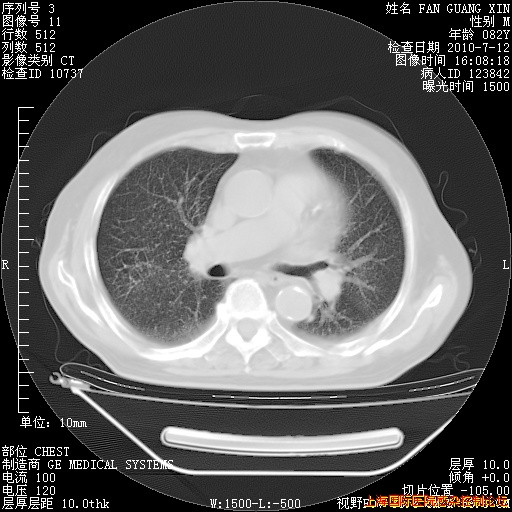

今天复查CT